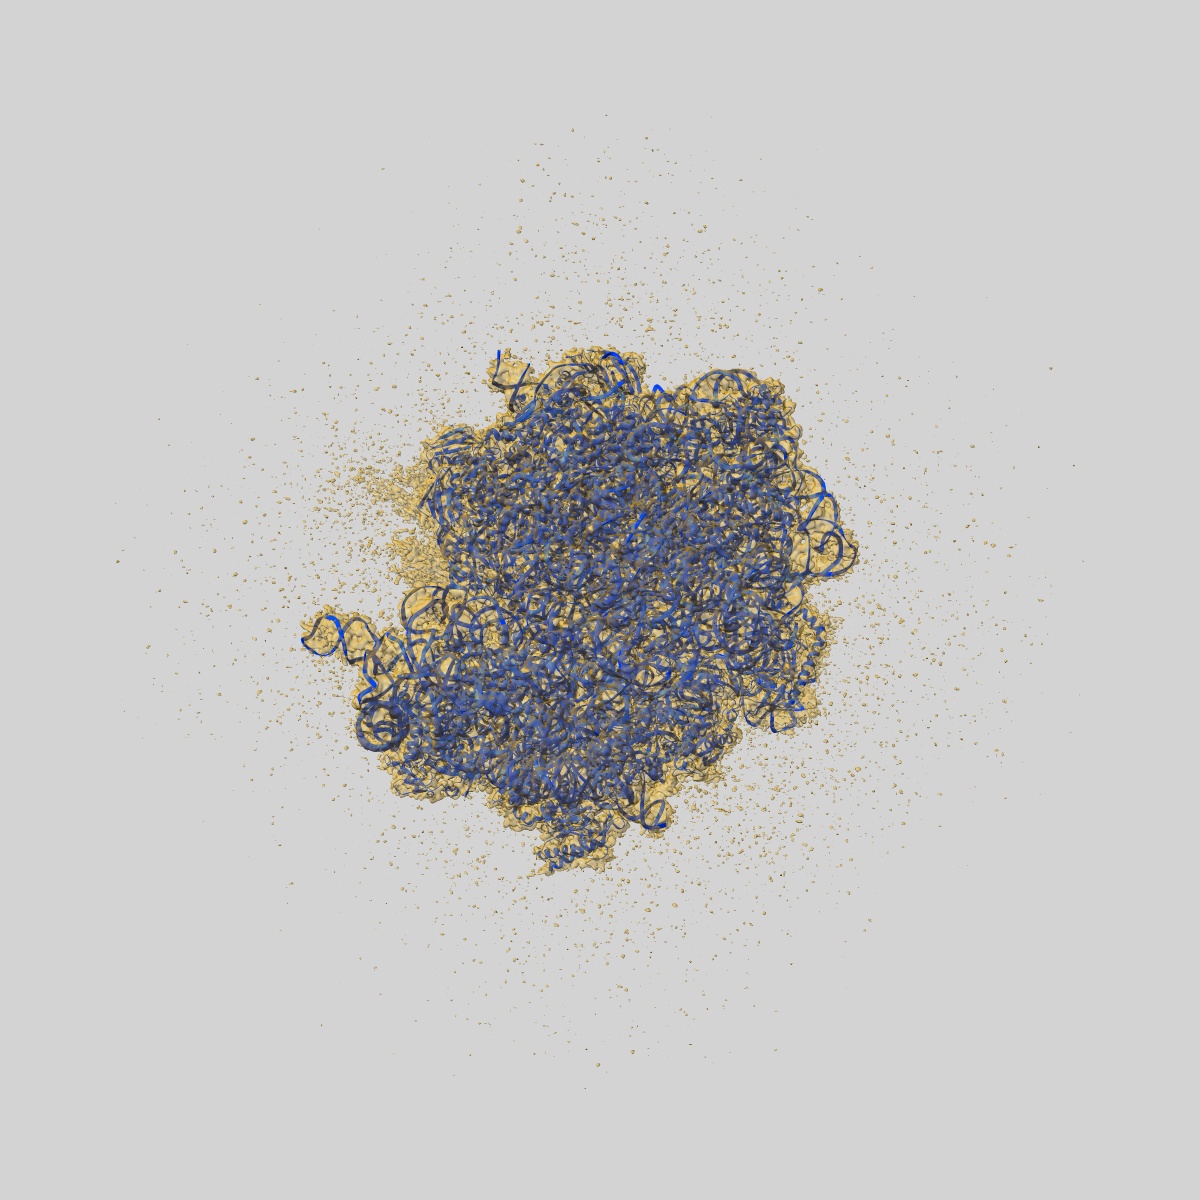

EMD-24803

Wild-type Escherichia coli ribosome with antibiotic radezolid

Single-particle2.47 Å

Sample: wild-type Escherichia coli ribosome with antibiotic radezolid

Structural basis for context-specific inhibition of translation by oxazolidinone antibiotics.

(2022) Nat Struct Mol Biol , 29 , 162 - 171